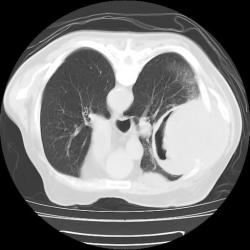

Правое легкое: в проекции средней доли (S3,4,5) определяется объемное образование преимущественно однородной структуры с ровными, четкми контурами размерами 92х88х94мм. Плотность его составляет 19-25 едН. В медиальных отделах образования содержится серповидная полоска воздуха. Латеральные отделы образования выходят за контуры грудной полости на 42 мм. На этом участке ребра не дифференцируются. Внутренний контур передней зубчатой, подлопаточной мышц размытый, граница между образованием и ними отчетливо не видна. Кзади от образования, в кортикальных отделах в легочной ткани инфильтрация. Кпереди от описанного образования расположен участок, широким основанием прилежащий к грудной стенке, имеющий плотность 12-20 ед.Н, однородную структуру, размеры 14х48мм. Прилежащее ребро интактно.